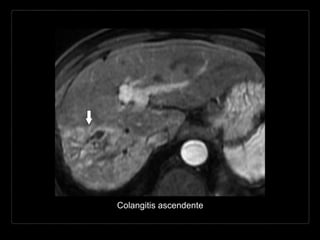

Colangitis ascendente

Hallazgos por TC

• cálculo obstructivo

• signo del “ojo de buey”

• dilatación de la vía biliar intra-/extrahepática

• engrosamiento y reforzamiento de la pared

• material intraductal hiperdenso (bilis purulenta)

• neumobilia

• pequeños abscesos hepáticos comunicados.

Hallazgos por RM

• T1

• cálculos hipointensos

• bilis hipointensa

• dilatación, estenosis,

engrosamiento de la

pared de la via biliar

• T2

• bilis hiperintensa

• hiperintensidad

parenquimatosa en

cuña o peribiliar

• MRCP

• defectos de llenado

hipointensos (cálculos)

entre la bilis hiperintensa

• estenosis irregulares,

dilatación proximal de los

conductos biliares